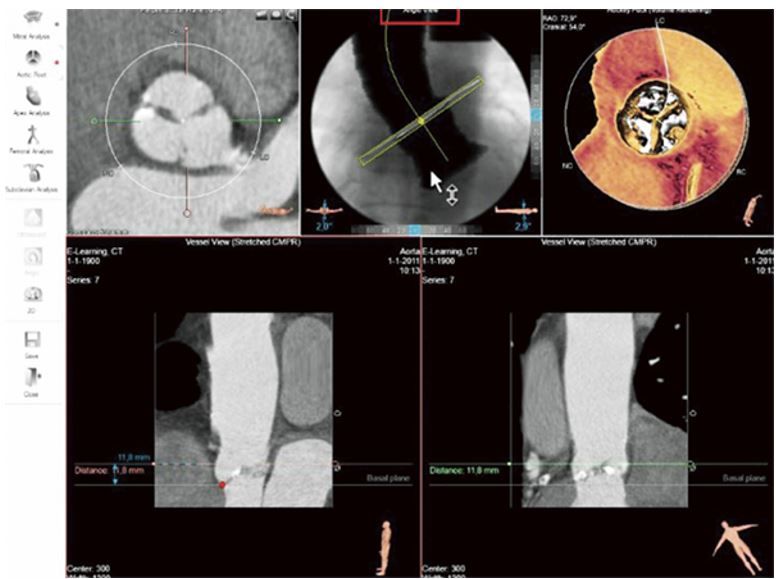

ПЗ 3mensio аортального клапану